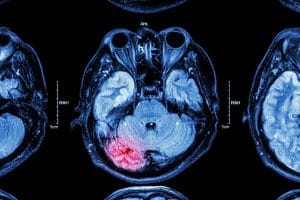

Can a New “Sniff Test” Help Unresponsive Brain Injury Victims?

Traumatic brain injury researchers, after many years of study and testing, have recently developed a new test that can improve the chances of performing a fast and accurate diagnosis of individuals with brain trauma. This test does not involve the application of some new state-of-the-art technology, but on a simple test of the senses. It is referred to as “the sniff test” and the results, published in April in Nature, highlight the importance of olfaction (smell) in brain function.

The sniff test adds to the diagnostic toolbox already present with standardized behavioral assessments and neuroimaging testing. These three tests combined provide medical professionals with the opportunity to reduce the high misdiagnosis rate involving traumatic brain injuries that leave individuals unconscious.